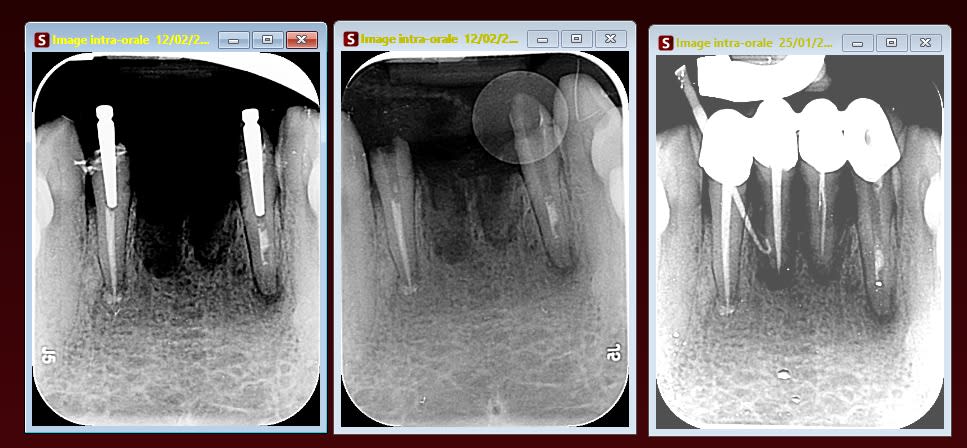

Ma titulaire m’a remonté les bretelles pour ce cas, je m’apprêtais à faire cela dans la même séance:

- extraction 41 et 31

- retraitement endo 32 et 42

-bridge provisoire

Puis réévaluation des 32, 42 et trouver des solutions prothétiques avec la patiente mais elle m’a dit que c’était grave d’un point de vu légal.

Ci-dessous les radios:

Et dans le cas que tu présentes il vaut mieux évaluer les dents avant interventions. ...Et entreprendre de faire un bridge sur les deux latérales qui ont une valeur extrinseque relativement assez faible est assez risqué, d'autant plus que le traitement canalaire de la 32 est assez "léger ".

Et avant ça je fais les RTE des latérales, car ici insuffisant et LIPOE sur mon scan.

Par contre il faudra que tu reprennes le rte de la 32 qui est insuffisant.

Mefie toi aussi d'une possible desmodontite, les incisives du bas sont, par expérience, souvent capricieuses surtout quand il y a des lésions chroniques préexistantes.